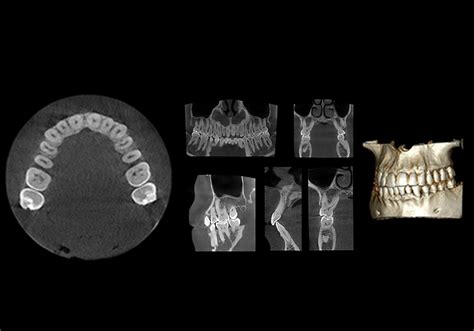

El CBCT dental (Tomografía Computarizada de Haz Cónico) es una técnica de imagenología avanzada utilizada en odontología para obtener imágenes tridimensionales detalladas de la boca, dientes, maxilares y estructuras óseas. Esta tecnología puntera ha revolucionado la forma en que los dentistas diagnostican y planifican tratamientos.

El CBCT emite rayos X desde diferentes ángulos para capturar una sección transversal de imágenes de la cavidad bucal del paciente. La fuente de rayos X y el detector, situados uno frente a otro en un brazo en forma de c o pórtico, giran a la vez en un barrido de 360º alrededor de la cabeza capturando múltiples imágenes. En una sola rotación puede tomar hasta 200 imágenes en 2D de alta resolución.

Nuestro escáner dental CBCT utiliza un haz cónico que captura imágenes en un solo giro alrededor de la cabeza del paciente. A continuación, las múltiples imágenes creadas se procesan digitalmente con la ayuda del software que incorpora el CBCT.

- Tecnología 3D y alta resolución: El CBCT proporciona imágenes tridimensionales en alta resolución. Las imágenes del CBCT son isotrópicas y están formadas por voxels (unidad mínima de información que es similar al píxel en fotografía).